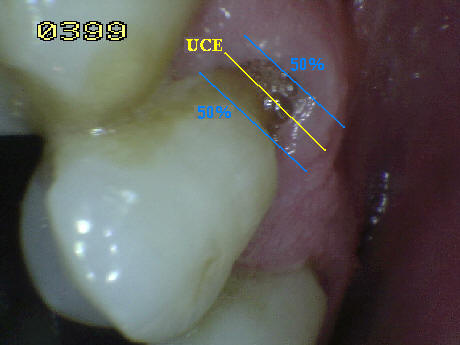

Consideraciones

especiales en la codificación de caries radicular:

- Cuando la superficie de la corona y la raíz estén afectada

por caries deben ser identificadas independientemente.

En caso de duda porque la lesión de caries se encuentra en la

unión cemento-esmalte (UCE) debe analizarse que superficie

esta más afectada o que se extienda por lo

menos 1 mm o más allá del limite de la unión cemento esmalte (UCE),

en ambas direcciones cervico-incisal y cervical apical, debe

considerase cual es la más extensa aplicando la regla del

50% , si existe igualdad el examinador debe decidir si la lesión

es codificada como de raíz o de corona, o en su defecto puede

aplicar ambas. Ver imagen derecha.